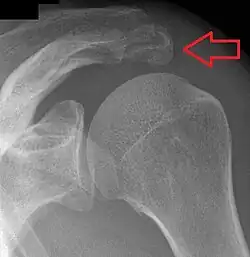

Shoulder

- An os acromiale forms when any of its four ossification centers fail to fuse. These four ossification centers are called (from tip to base) pre-acromion, meso-acromion, meta-acromion, and basi-acromion. In most cases, the first three fuse at 15–18 years, whereas the base part fuses to the scapular spine at 12 years. Such failure to fuse occurs in between 1% and 15% of cases.[23][24] It rarely causes pain.